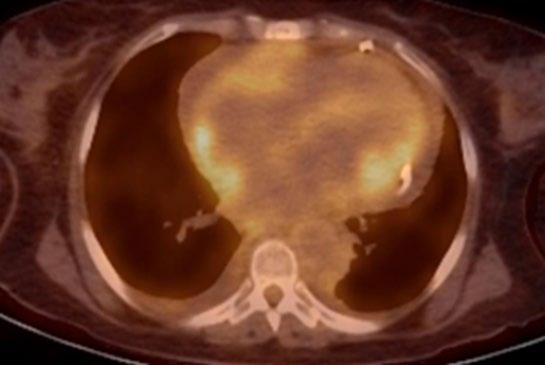

Radiogenomics Relationship of Nonsmall Cell Lung Cancer: Preliminary Results

Citation: EMJ Radiol. 2024;5[1]:24-25. https://doi.org/10.33590/emjradiol/10304578.

BACKGROUND AND AIMS

Radiomics, an emerging paradigm in medical imaging, entails the quantitative analysis of tumour features, and has exhibited potential in predicting treatment responses and outcomes. Furthermore, within the domain of -omics assessments, the significance of comprehensive genetic evaluation in non-small cell lung cancer (NSCLC) is on the rise, influenced by both biological and therapeutic considerations.

The aim of this study was to correlate radiomics features with the genetic results obtained from liquid biopsy in patients with lung tumours. The prediction of tumour genetics in radiomics relies on the presumption of conducting a non-invasive evaluation of molecular characteristics in tumour tissues, which can be challenging in certain tumour types, such as NSCLC. Therefore, in this context, the authors considered it pertinent to explore and generate hypotheses regarding the technical feasibility of identifying associations between genomics acquired through liquid biopsy assessments and radiomics.

MATERIALS AND METHODS

This observational, prospective study integrated radiomic perspectives using CT and genomic perspectives, through next-generation sequencing applied to liquid biopsies.

The authors included 62 patients with NSCLC who underwent pre-surgery CT (Revolution™ 128 MDCT, GE HealthCare, Chicago, Illinois, USA) at the Radiology Department of Campania University Luigi Vanvitelli, Naples, Italy. Every patient for whom liquid biopsy was performed gave informed consent for the genetic analysis. For the radiomic analysis, image processing CT volumes were manually delineated using ITK-SNAP 3.8.0 (University of Pennsylvania, Philadelphia, USA). Radiomics features (first order: Gray Level Co-occurrence Matrix, Gray Level Run Length Matrix, Gray Level Size Zone, Gray Level Dependence Matrix, and Neighbouring Gray Tone Difference Matrix) were computed using Pyradiomics1 in Python 3.7 (Python Software Foundation, USA) environment.

Radiomic features were derived from CT images, and genetic assessments were performed using a comprehensive panel targeting 523 cancerrelated genes. For the statistical analysis, association between radiomic features and gene mutations were assessed using feature importance based on receiver operating characteristic curve analysis; moreover, a machine learning approach based on support vector machine was used to evaluate the ability of radiomic features to predict gene mutations.

Associations between radiomic features and genetic mutations were established using the area under the receiver operating characteristic curve. Machine learning techniques, including support vector machine classification, aimed to predict genetic mutations based on radiomic features. The prognostic impact of selected gene variants was assessed using Kaplan–Meier curves and log-rank tests.

RESULTS

Sixty-two patients underwent screening, with 53 being comprehensively characterised radiomically and genomically. This group was predominantly male (68.4%), and adenocarcinoma was the prevalent histological type (73.7%). Most patients exhibited ECOG Performance Status of 0 or 1 (87.7%), and 91.2% had a history of former or current smoking. Disease staging was distributed across I–II (38.6%), III (31.6%), and IV (29.8%). Significant correlations were identified with mutations

Abstract ● ECR 2024 24 Radiology ● April 2024 ● Creative Commons Attribution-Non Commercial 4.0

of ROS1 p.Thr145Pro (shape_Sphericity), ROS1 p.Arg167Gln (glszm_ZoneEntropy, firstorder_TotalEnergy), ROS1 p.Asp2213Asn (glszm_GrayLevelVariance, firstorder_ RootMeanSquared), and ALK p.Asp1529Glu (glcm_Imc1). Patients with the ROS1 p.Thr145Pro variant demonstrated markedly shorter median survival compared to the wild-type group (9.7 months versus not reached; p=0.0143; hazard ratio: 5.35; 95% confidence interval: 1.39–20.48).

CONCLUSION

This study contributes to advancing the prediction of cancer genetics through the application of non-invasive radiomic techniques. The prediction of tumour genetics in radiomics hinges on the assumption of conducting a non-invasive assessment of molecular characteristics in tumour tissues, which can pose challenges in certain tumour types, such as NSCLC. Therefore, within this context, the authors deemed it relevant to explore and formulate hypotheses regarding the technical feasibility of identifying associations between genomics obtained through liquid biopsy assessments and radiomics.

Specific radiomic features illustrate the capability to predict non-synonymous mutations of ROS1 and ALK in patients with NSCLC. Investigating the prediction of cancer genetics using non-invasive radiomic techniques represents an innovative frontier in scientific research, which is currently undergoing extensive investigation. Research on the use of conventional CT features and CT image-based radiomic features to predict the gene mutation status of lung cancer is still in its nascent stages.

The integration of radiomic techniques in predicting cancer genetics holds potential, but is constrained by cost and technological limitations. Despite these challenges, the authors’ study explores the relationships between genomics and radiomics, revealing specific genetic variants associated with radiomic features. While acknowledging limitations, particularly the small sample size and the lack of actionable mutations, this research lays the groundwork for broader investigations aiming to link radiomics and genomics in NSCLC. The ultimate objective is to improve prognostic accuracy and refine therapeutic strategies. ●